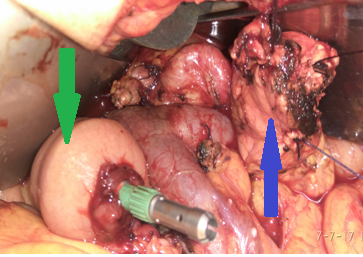

After completion of the pancreatic head resection, the following are demonstrated: (brown arrow) the AAA sac, (blue arrow) the confluence of the superior mesenteric vein with the splenic vein and the formation of the portal vein, and (green arrow) the body of the pancreas (Courtesy Dr. V. Penopoulos)

Blue arrow – The body of the pancreas, fully mobilized, ready for the pancreaticogastric anastomosis, and Green arrow – Jejunal loop, ready for the gastrojejunal anastomosis (Courtesy Dr. V. Penopoulos)

Completion of the pancreaticogastric anastomosis – Green arrow – demonstrates the pancreas secured within the gastric lumen (Courtesy Dr. V. Penopoulos)